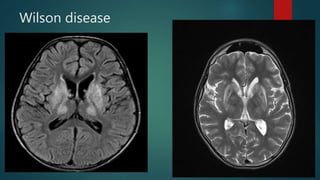

Wilson disease